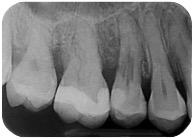

Sì, perchè ora faccio il figo, ma nel non lontano 2011, mi arriva una paziente con questo dente.

E questa è stata la mia reazione.

Cosa caspita era capitato a questo dente? Allarmato faccio vedere la radiografia a Federico, il mio socio, e anche lui pensa a qualcosa di brutto. Che so, un tumore di quelli incomprensibili che avevamo studiato solo sui libri di radiologia che si era insinuato all’interno di questo 4.6! ???